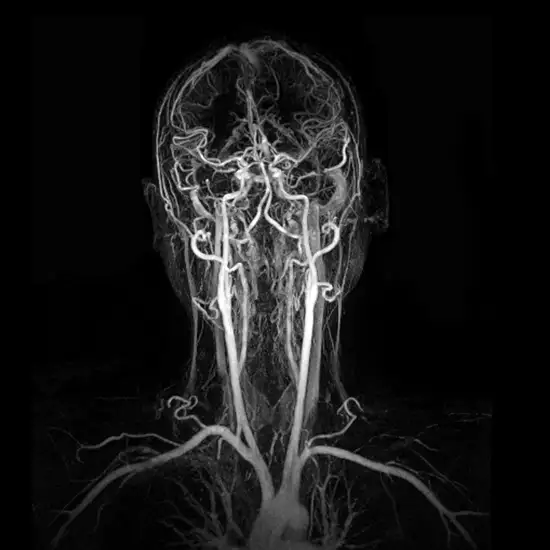

An MRA of the neck (carotid) is used to create images of soft tissues, bones, and internal body components. MRA of the neck is mainly used to detect arterial constriction. Using MRA of the neck, two three-dimensional pictures of the blood vessels are created.

The two carotid arteries, the major blood channels that supply the head and brain with blood and oxygen, can be seen in detail on a carotid magnetic resonance angiography (MRI) scan.